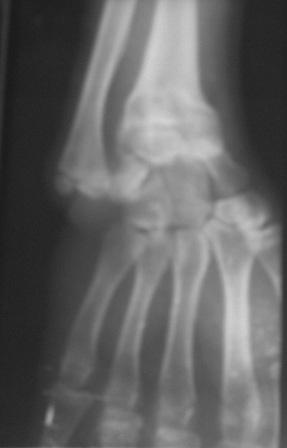

Доброго времени суток уважаемые коллеги! Обратился б-ной 16

лет.Травму получил 9 лет назад, перелом лучевой кости и надмышелковый

перелом плеча. Имеется деформация л/з сустава типа лучевой

косорукости, укорочение п/плечья, отсутствия локтевой девиации,

cubitus varus под углом 25гр. Просит первоначально исправить

деформацию л/з сустава и восстановить длину п/плечья. Наш план-

остеотомия дистального метафиза лучевой кости, коррекция деформации и

удлинение по методу Илизарова. Уважаемые коллеги, помогите советом!

Может быть, есть какие-то нюансы , или другие методы? Снимки

прилагаются.